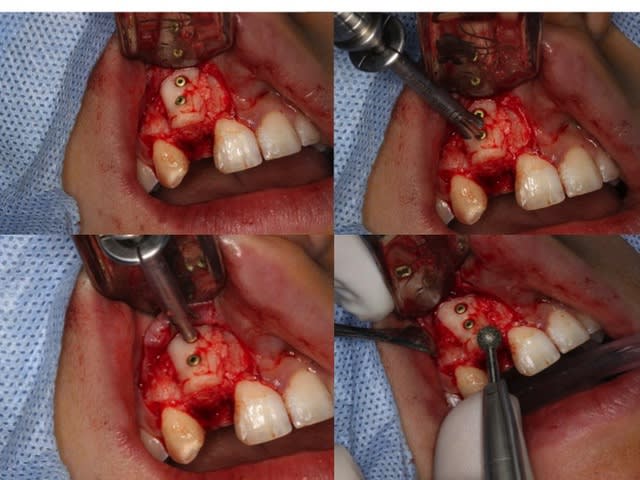

Greffe 2D:

Greffon mince en vestibulaire qui coulisse sur les deux vis, on écarte du SR ( photo avec syndesmotome faucille) on glisse dessous les fragments copeaux d'os et on ressert un peu à la fin

Donc le greffon cortical sert de membrane pour protéger le lit de copeaux

Le photos sont dans l'ordre de réalisation

Prélèvement rétromolaire/ramique

Nettoyage du SR avec fraise boule pour retirer tout les tissus fibreux sur l'os et accessoirement ouvrir les espaces médullaire ( en théorie ) Ici grosse frayeur car l'apex de 11 est dans le vide ainsi que la moitié de la dent: toute la face vestibulaire et distal... Merci Mrs les ortho.....

Séparation du greffon en deux et mise en forme

Préparation des trous de vis en diam 1,5 pour vis de 1,3 et cuvette pour les têtes de vis

Pince de barth pour maintenir le greffon et forage dans les trous au forêt de 1mm et mise en place des vis. Le greffon est libre, pour pouvoir régler l'épaisseur souhaitée.

Broyage du reste du prélèvement

Le greffon est soulevé pour glisser dessous le broyât osseux

Serrage final des vis et élimination des angles tranchants à la fraise boule diamantée

Libération du lambeau avec une lame 15 neuve

Contrôle de la passivité du lambeau en position

Suture et PAP une dent